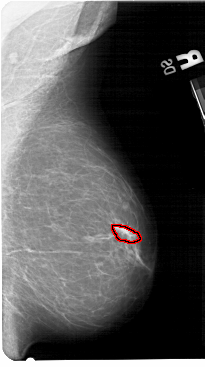

A_1548_1.RIGHT_MLO

FILE: A_1548_1.RIGHT_MLO.OVERLAY

TOTAL_ABNORMALITIES 1

ABNORMALITY 1

LESION_TYPE CALCIFICATION TYPE PUNCTATE DISTRIBUTION LINEAR

ASSESSMENT 3

SUBTLETY 1

PATHOLOGY BENIGN

TOTAL_OUTLINES 1

BOUNDARY